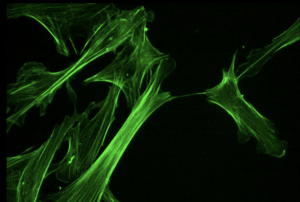

La proteine TAU

Dans les années 1980, on n’était pas certain de la nature des dégénérescences neurofibrillaires, très présentes dans les neurones des patients Alzheimer. L’hypothèse dominante voulait qu’elles soient constituées d’éléments du cytosquelette. En 1985, Jean-Pierre Brion trouve un anticorps qui marque de façon sélective les dégénérescences neurofibrillaires de cerveaux Alzheimer, non pas en s’attachant directement avec des protéines du cytosquelette qui donnent leurs formes aux neurones, mais bien avec la protéine Tau « Tubulin Associated Unit » (en anglais) qui stabilise les cytosquelettes. D’autres équipes confirmèrent par la suite que la protéine Tau est l’élément principal des dégénérescences neurofibrillaires.